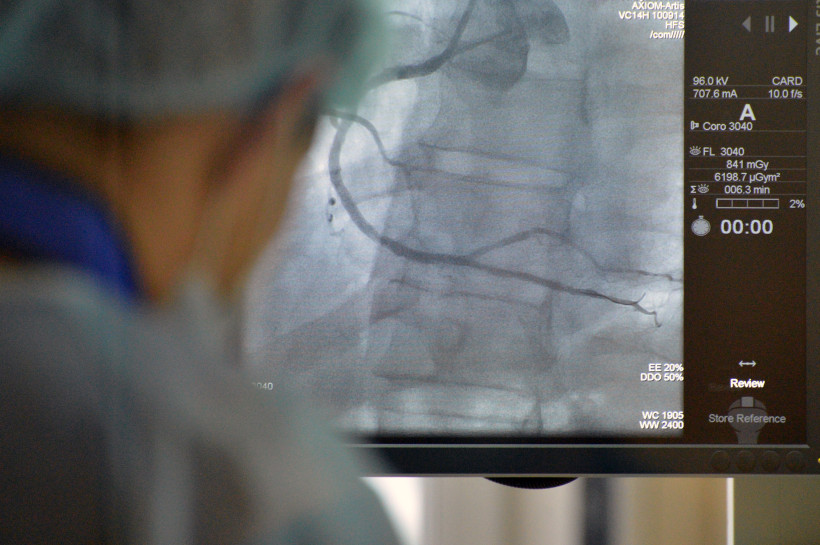

Очень сложным пациентам в клинике кардиохирургии Амурской государственной медицинской академии (АГМА) за две недели провели десять операций на работающем сердце. Часть из них прошли впервые. Подобные операции выполняются далеко не в каждом кардиохирургическом центре даже в центральной части России.

Это были больные с клапанными пороками и с ишемической болезнью сердца, а также с сочетанными нарушениями сердечной деятельности. Как рассказал заведующий клиникой кардиохирургии к. м. н. Евгений Тарасюк, прежде некоторые категории таких пациентов клиника вообще не брала оперировать, а сегодня это стало возможным благодаря помощи коллеги специалиста-кардиохирурга из Красноярска. Несколько операций выполнили впервые — трехсосудистое шунтирование коронарных артерий на работающем сердце без применения аппарата искусственного кровообращения, рассказали в АГМА.

— Лечение ишемической болезни проводилось на работающем сердце, — пояснил заведующий клиникой. — Хотя обычно эти оперативные вмешательства выполняются при искусственном кровообращении. При открытой операции на работающем сердце, как правило, выполняется шунтирование только одной коронарной артерии. Мы же выполняли на двух и даже трех, к тому же параллельно проводилось и лечение нарушения ритма сердца. Часть операций выполнена без применения искусственного кровообращения, что очень хорошо прежде всего для самого пациента: все риски были сведены к минимуму.

Учитывая сложность оперативных вмешательств, сердечно-сосудистые хирурги клиники кардиохирургии  Александр Филиппов и Валентин Филатов совместно с красноярским коллегой оперировали больных в среднем от двух до пяти часов. И все операции прошли успешно.